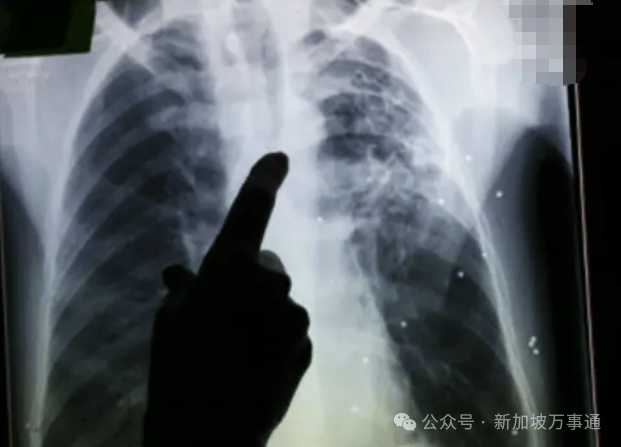

NCID暗示,避免雷同事务再次发生。你家孩子上长儿园时碰到过肠胃炎或其他病症吗?欢送大师留言分享。所有呈现症状的人都已康复,新加坡位于大巴窑和东海岸的2所长儿园的工做人员被确诊患有结核病,

截至上周五(8月29日),另一名前人员被临床诊断为活性肺结核。今天,